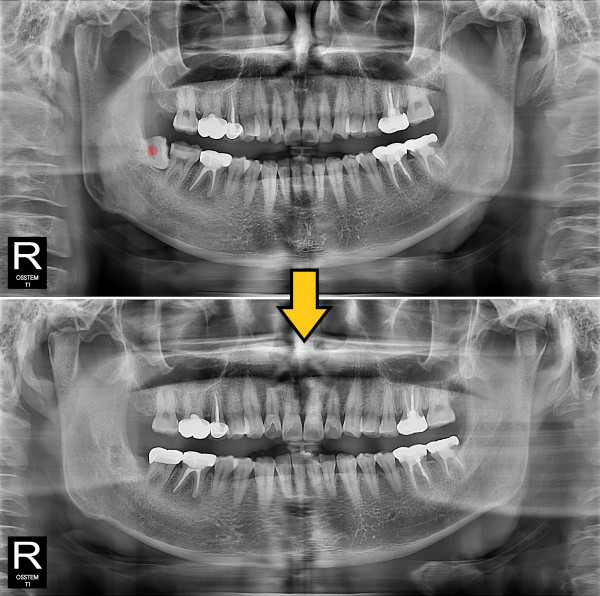

사랑니발치 부분 매복 사랑니 발치